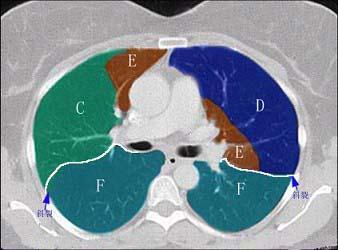

问题 结合肺段模式肺动脉干与右肺动脉层面、心室层面、主动脉弓层面、左右心房层面图(如图),选出左肺下叶的组成 ( )

选项 A.G+H+I+J B.F +H+I+J C.E+F+G+H+I+J D.D+E+F+G+H+I+J E.C+D+E+F+G+H+I+J

答案 B